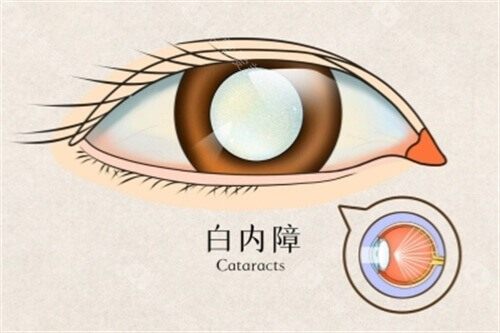

白内障是一种常见的眼科疾病,尤其在老年人群体中发病率较高。

当病情发展到一定程度,手术治疗是目前比较有效的方法。